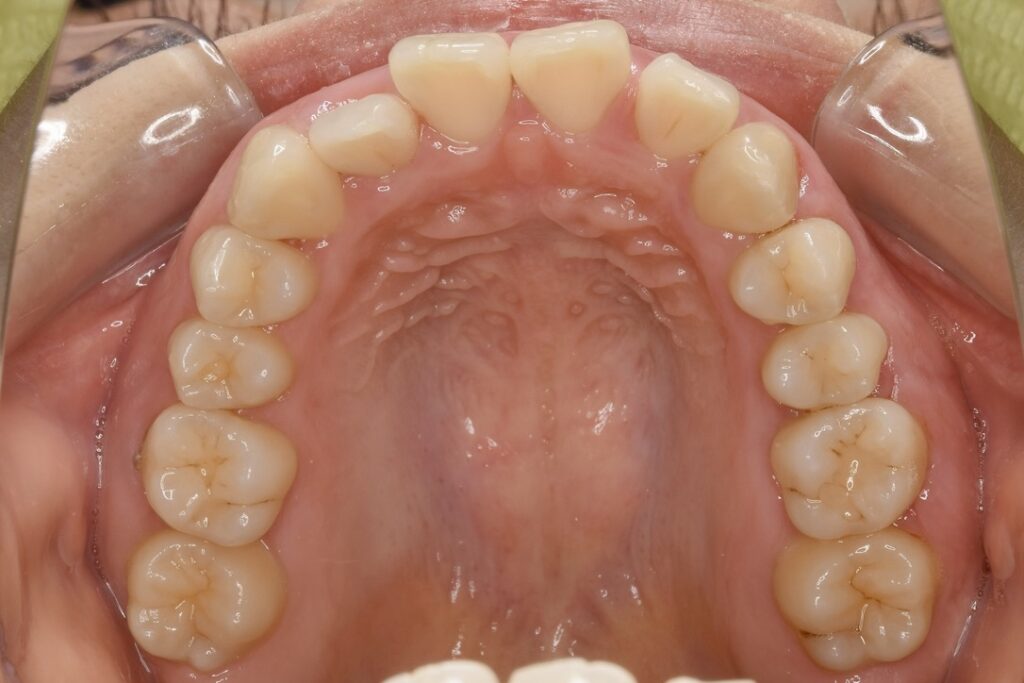

21歳 女性 治療期間:1年1ヶ月

叢生(ガタガタ)

マウスピース矯正装置(インビザライン)

非抜歯

BEFORE

AFTER

診断名・主な症状

叢生

治療内容

上下とも歯並びの横幅を広げながら、でこぼこを解消しました。

マウスピース矯正(インビザライン)

抜歯あり(智歯抜歯)

治療期間

1年1ヶ月

通院回数

10回

費用

85万円程度(税別)

リスク・副作用

痛み、歯肉退縮、歯根吸収、抜歯に伴う出血や腫れが生じることがあります。